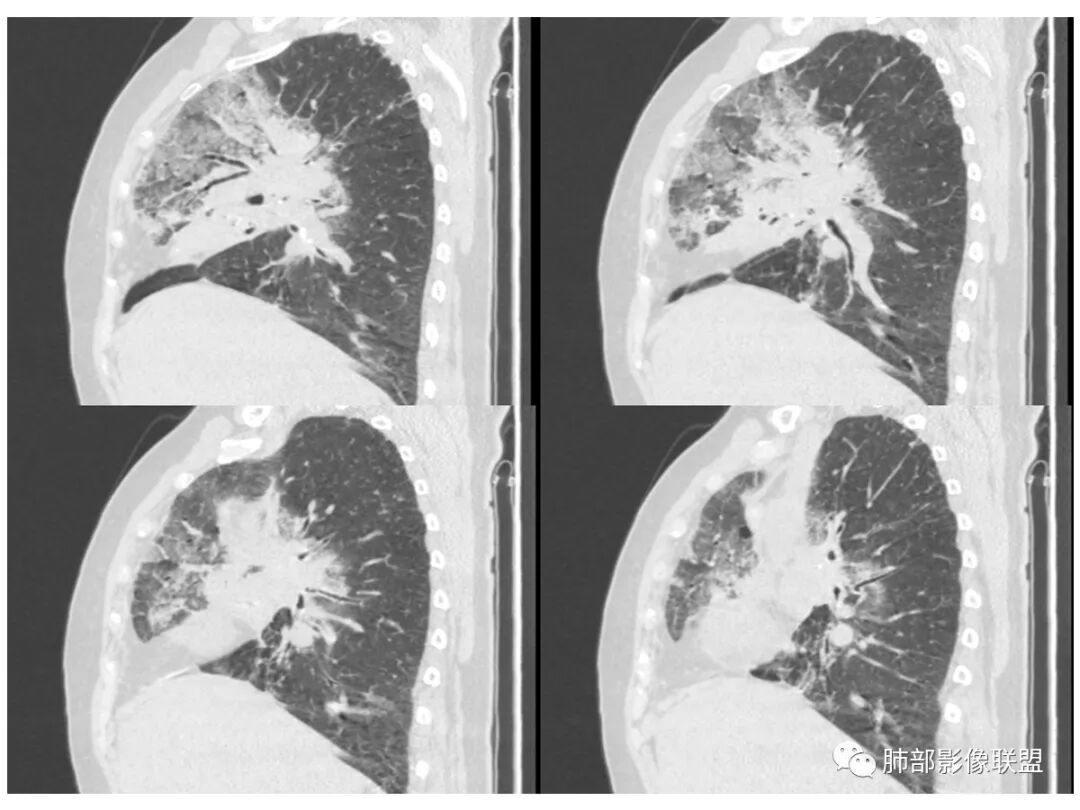

右肺上叶大片状阴影,内见僵硬的支气管,部分支气管轻度扩张,内见一空洞和液平,病灶边缘可见磨玻璃影,首先考虑恶性病变,粘液性腺癌伴感染可能。

老年女性,右肺上叶大片实变及磨玻璃密度影,磨玻璃边缘清晰,内可见小叶间隔增厚,内可见空洞,似可见分隔,叶间裂局部膨隆,纵膈窗,没有增强,枯树枝不明显,肺炎型肺癌可能,鉴别大叶性肺炎,结核?

胸CT:右肺上叶实变内可见支气管充气征,近端支气管狭窄,远端扩张,周围可见毛玻璃影,右肺中叶支气管闭塞,并可见气道壁钙化,右肺中叶体积缩小,实变内可见空洞,并可见气液平面,空洞周围可见毛玻璃样影,右肺下叶支气管开口狭窄,右肺门淋巴结肿大。纵隔窗可见病灶与壁层胸膜间隙增宽,考虑良性病变-----感染性病变------TB?

1.右上肺大片状影,周围有磨玻璃影,支气管截断征、枯枝征、远端支气管充气征,可见多个大小不等囊泡(支气管阻塞活瓣作用形成),病灶有少许收缩力感,叶间裂被稍牵拉内移;

病史老年女,白痰;影像实变,ggo多数边界清,病灶下缘部分不清,枯树枝,支气管近端阻塞、僵硬,病灶跨叶;病灶内空洞,有液平;间质增厚有结节感;肺炎型肺癌大于干酪性肺炎。

老年女性,慢性病程,咳嗽伴白色粘液痰,无发热腹痛,糖尿病,白细胞及C反应蛋白不高,血沉快,铁蛋白高。胸部CT,右肺上叶大片状实变伴磨玻璃密度影,边界不清,边缘局部膨隆,叶裂弧形下坠,实变影宽基底与胸膜相贴;右肺下叶前基底段见类似病灶;右肺中叶不张并空洞形成,空洞内见气液平面;综合考虑右肺上叶及下叶肺炎型肺癌,右肺中叶结核。

老年女性,病史1月,右肺上中叶大片状影,跨叶,上叶为主,磨玻璃为主,边界模糊,部分实变,内见空洞影和液气平面,壁光滑,支气管开口狭窄,局部有扩张,右肺门淋巴结钙化,首先考虑感染性病变,结核可能,鉴别粘液腺癌。

白色粘液痰,枯树枝,支气管僵直,有空洞,磨玻璃,叶间裂膨隆、下坠,吴婧老师的肺炎型粘液性腺癌十大特点中占了好多条,所以考虑粘液腺癌,就差增强看看强化如何,血管如何了

患者老年女性,亚急性起病,胸部CT:右肺上叶大片实变,可内见坏死性空洞,可见mGGO,GGO边缘清晰,局部彭隆,内见支气管充气征,可惜没增强,粘液腺癌要考虑,但病灶明显是内朝外不支持,综合考虑结核,建议查痰找抗酸杆菌、气管镜

老年女性,咳白色粘液痰,右肺跨叶大片高密度影,密度不均匀,其内见支气管枯树征,有空洞,边缘部分清楚,叶间裂有下坠膨隆感。考虑粘液腺癌,鉴别干酪性肺炎